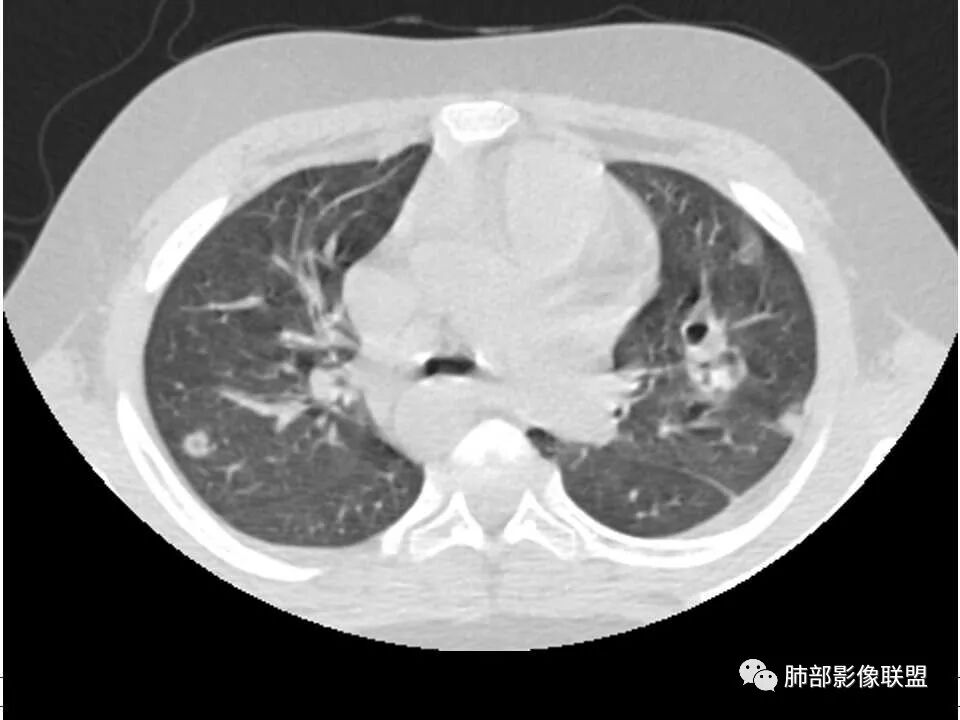

晨读,儿童,起病急,病程短,有下肢疼痛伴肿胀病史,发热,白细胞升高,结合下肢辅查,考虑骨髓炎,胸部ct:双肺多发空洞,结节,外带下叶为主,空洞内外光滑,无丝状物,有血管滋养征,综合病史及影像考虑脓毒性肺栓塞,金葡可能性大,建议痰培养,血培养,必要时ngs。

儿童患者,右下肢肿痛、发热起病,血象升高,双肺多发结节影,右肺结节并囊腔或空洞,左肺多发实性结节以胸膜下分布为主,考虑感染性病灶,有右下肢肿胀,需考虑蜂窝织炎, 血源性肺播散,金葡感染可能性大?

双肺多发结节,空洞,与胸膜相连,血道来源,空洞内壁光滑,结节周围模糊,考虑金葡菌感染。

患者儿童,因右下肢疼痛伴肿胀14天就诊。病程中有发热及伴随症状。膝关节MRI提示右侧膝关节及右髌骨髁异常信号影,右膝髌上囊及关节腔内少量积液。胸部CT:双肺胸膜下多发结节影,部分结节空洞形成,且结节周围可见血管集束征。综合考虑血源性脓毒性肺栓塞、坏死性肺炎。右侧骨髓炎、血播性金葡菌肺炎,鉴别其他特殊感染及血管炎。

胸部ct:双肺多发空洞,结节,外带下叶为主,空洞内外光滑,有血管滋养征,综合病史及影像考虑脓毒性肺栓塞,结合病史,金葡可能性大。

小儿,急性起病,下肢疼痛,mr提示骨髓水肿,临床化验炎性指标高,考虑金葡菌骨髓炎,双肺多发结节,以血管支气管束及胸膜下分布为主,部分结节近端与血管相连,部分结节可见空腔,内壁光整,部分囊腔有张力,考虑骨髓炎并肺内血播感染,金葡?

2.双肺多发片影,随机分布,多空洞或囊腔,胸膜下多楔形影,气道未见受累等等符合脓毒血症影像学表现,尤其是金葡。